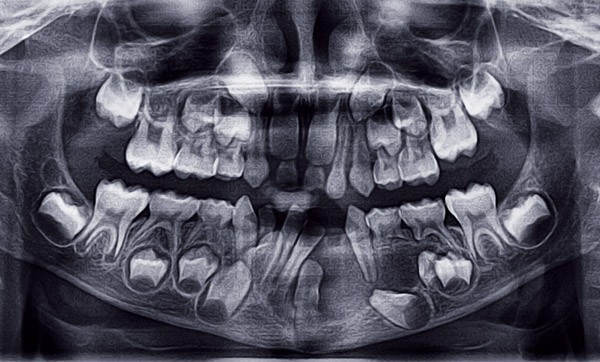

L’inclusion dentaire multiple est rare et est peu décrite dans la littérature scientifique. Le diagnostic de ces inclusions est non seulement clinique mais aussi radiologique. L’imagerie tridimensionnelle y joue d’ailleurs un rôle important. Elle affine le diagnostic et le plan de traitement, permettant ainsi des résultats plus prédictibles dans ces situations cliniques complexes. La prise en charge de ces dents incluses multiples augmente considérablement la durée du traitement. Elle demande à la fois une bonne communication entre le chirurgien oral et l’orthodontiste, et également une coopération importante de la part du patient et des parents. Après avoir décrit le diagnostic et les options thérapeutiques des inclusions multiples, nous présenterons deux cas d’inclusions multiples de dents permanentes.

L’inclusion dentaire multiple est rare et est peu décrite dans la littérature scientifique [1]. Les étiologies les plus fréquentes de l’inclusion sont locales. La présence d’inclusions multiples de dents permanentes est aussi corrélée à des syndromes génétiques ou des pathologies métaboliques ou hormonales. Dans certains cas, aucune étiologie n’est retrouvée.

Lorsqu’un patient se présente avec une inclusion dentaire unique ou une agénésie, cela augmente la difficulté du traitement orthodontique [2]. De ce fait, lorsque plusieurs dents permanentes sont incluses, la prise en charge et la durée du traitement augmentent considérablement [1, 3, 4]. Il est donc impératif de coordonner la séquence d’éruption de chacune de ces dents incluses. Pour cela, la communication entre l’orthodontiste et le chirurgien oral est indispensable afin de recourir à la technique chirurgicale et orthodontique la plus adaptée. Après avoir décrit la démarche diagnostique et les options thérapeutiques des inclusions multiples, nous présenterons deux cas d’inclusions multiples de dents permanentes.

L’ordre d’inclusion des dents permanentes est le suivant [5] : dent de sagesse mandibulaire, dent de sagesse maxillaire, canine maxillaire, prémolaire maxillaire et mandibulaire, incisives maxillaires, canines mandibulaires, incisives mandibulaires, première molaire maxillaire et mandibulaire et enfin deuxième molaire maxillaire et mandibulaire.

Si l’on écarte l’inclusion des dents de sagesse qui représente 55-65 % des cas d’inclusions, la dent la plus incluse dans la population générale est la canine maxillaire avec 0,9 à 3 % des inclusions. L’inclusion canine est le plus souvent palatine (61 à 90 % des inclusions) ; l’inclusion bilatérale est de l’ordre de 8 à 10 % et il existe des variations ethniques et une prédominance féminine (2F : 1H) [3, 6-15].